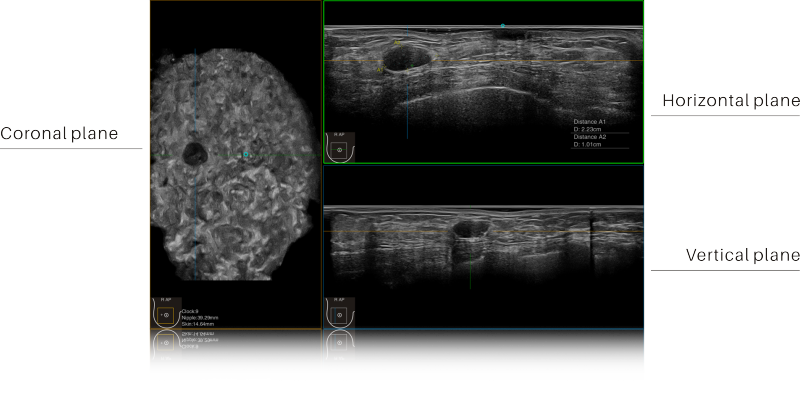

- Free 3D imaging displays coronal, transverse, and sagittal planes, reducing the misdiagnosis rate

Full Volume Imaging and Coronal Section with High Clinical Value

IBUS acquires volume data from multiple sections to provide abundant information. The coronal section intuitively shows the anatomical information of breast tissue in a supine position during operation, which helps surgeon to perform more accurate surgical planning.